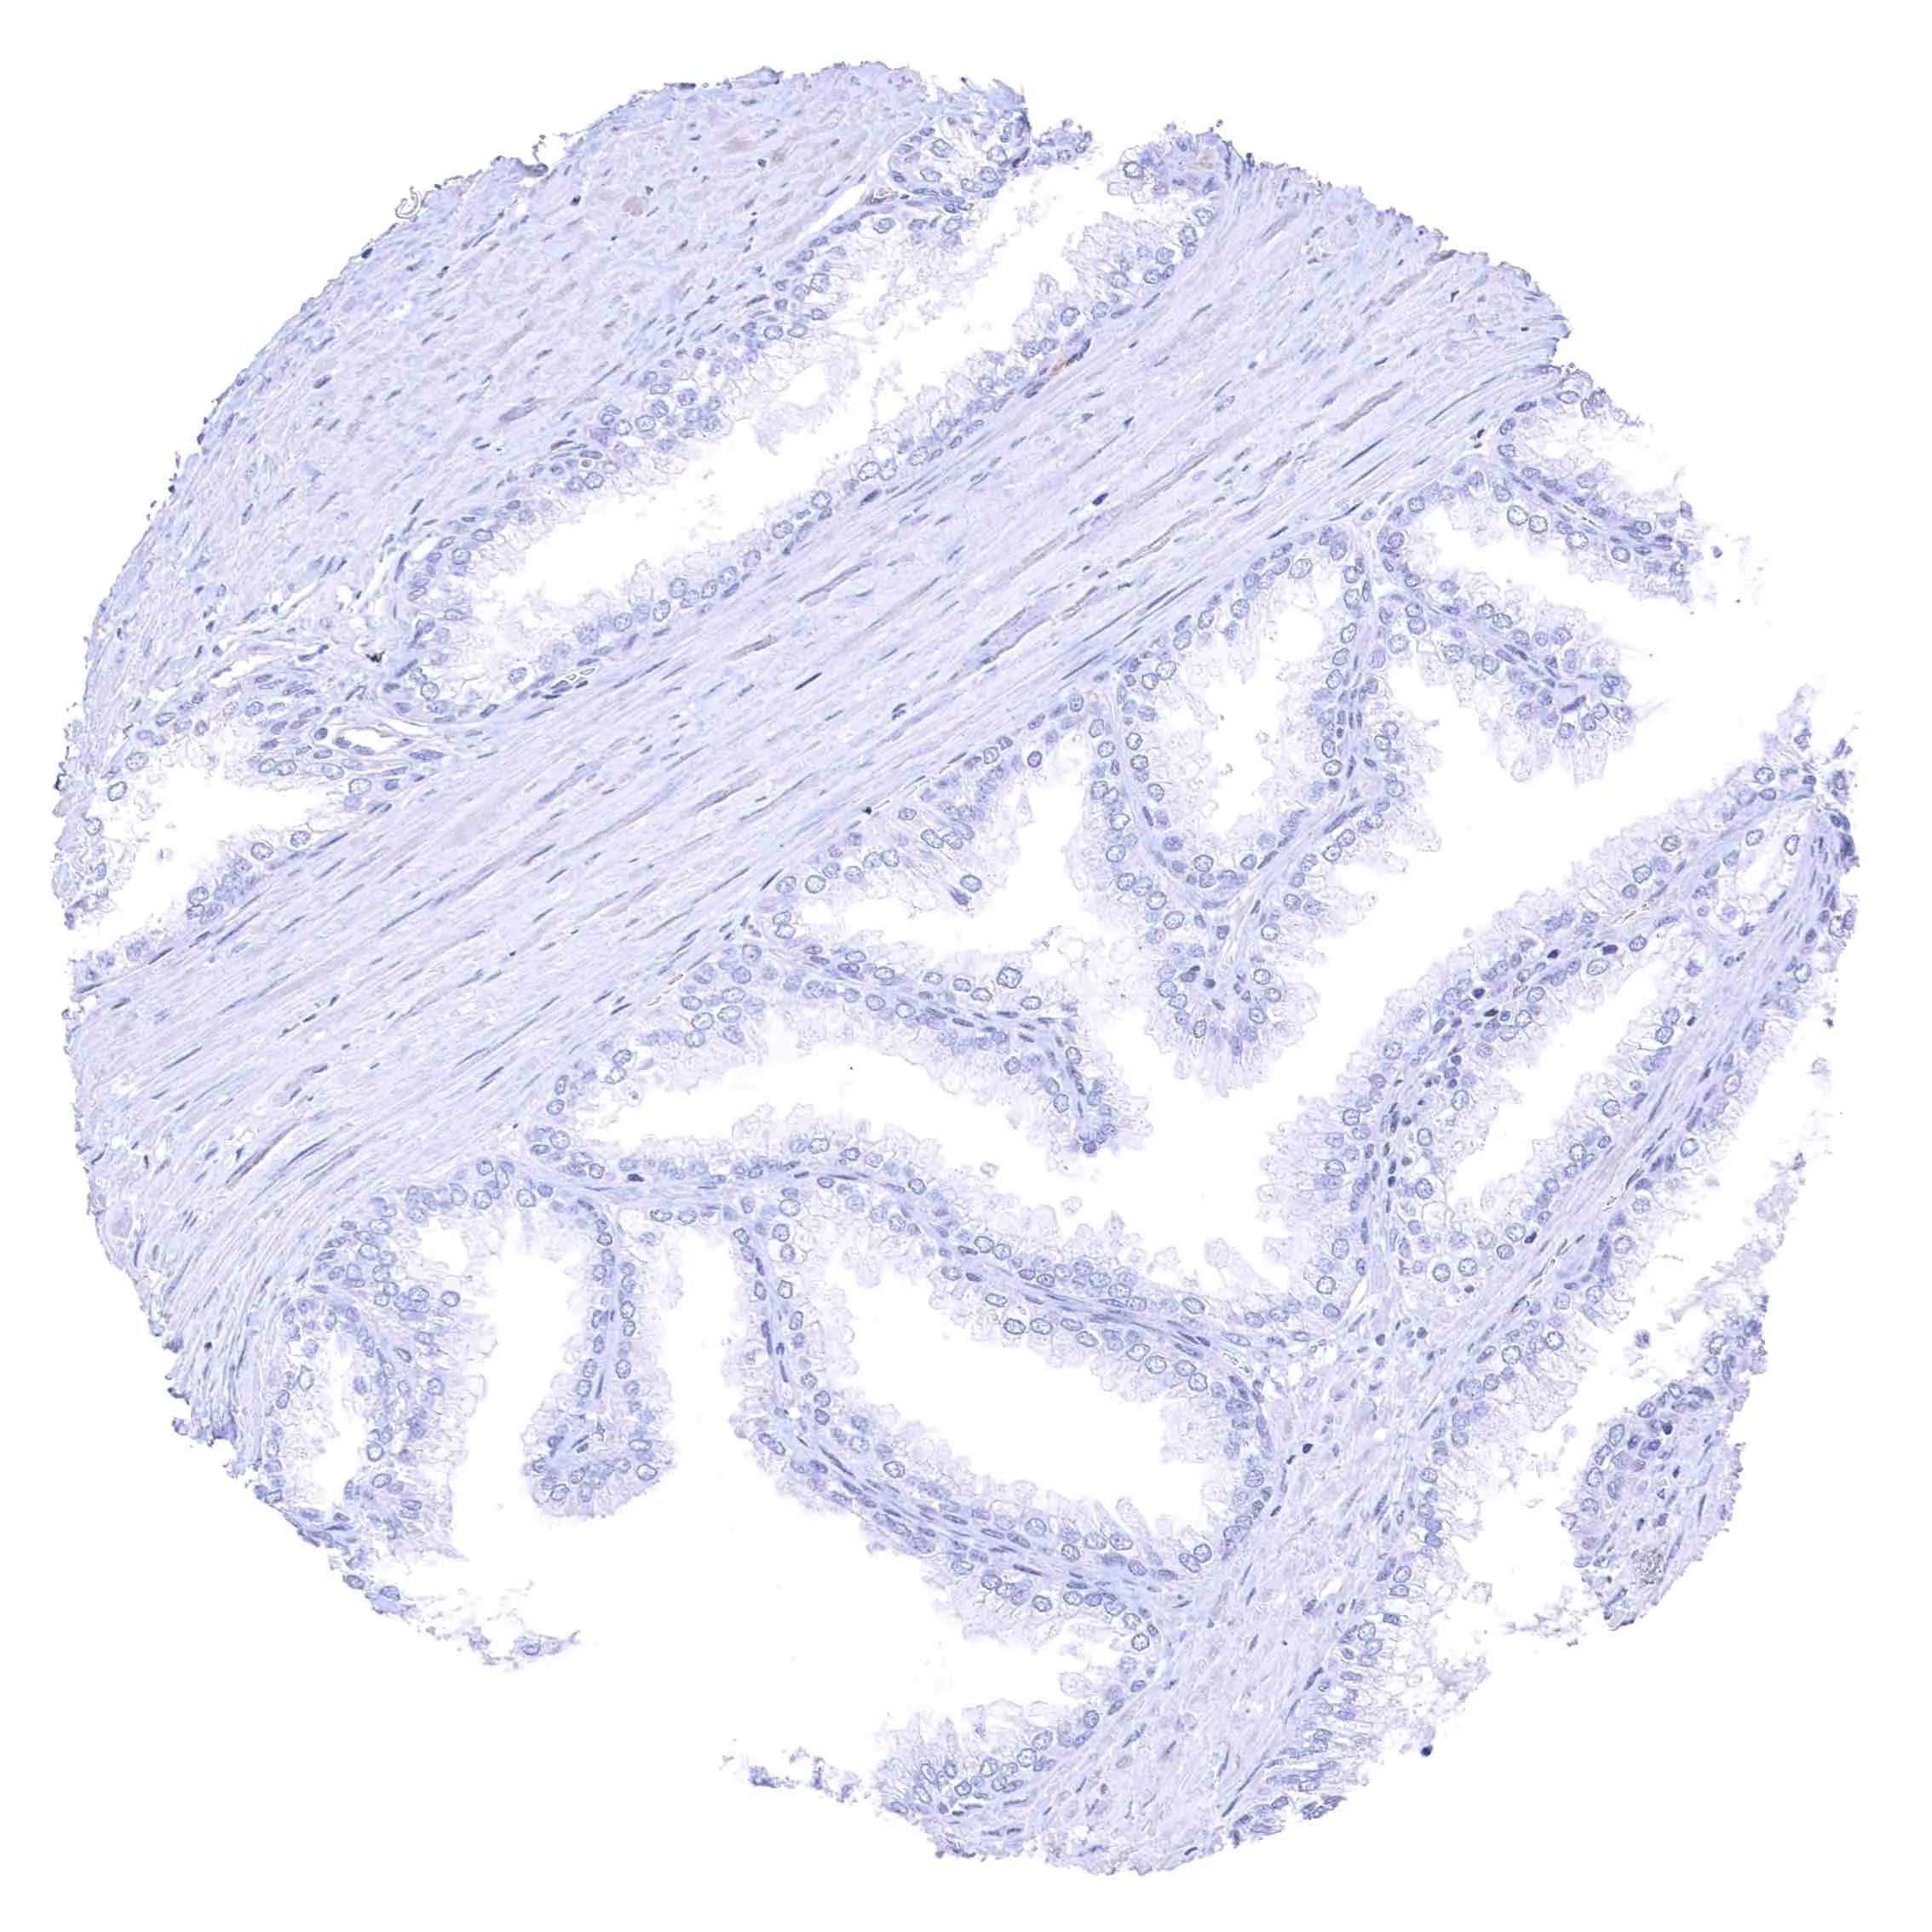

Fallopian tube, mucosa – Weak membranous NPR-C staining at the luminal cell border of endothelial cells of small blood vessels.